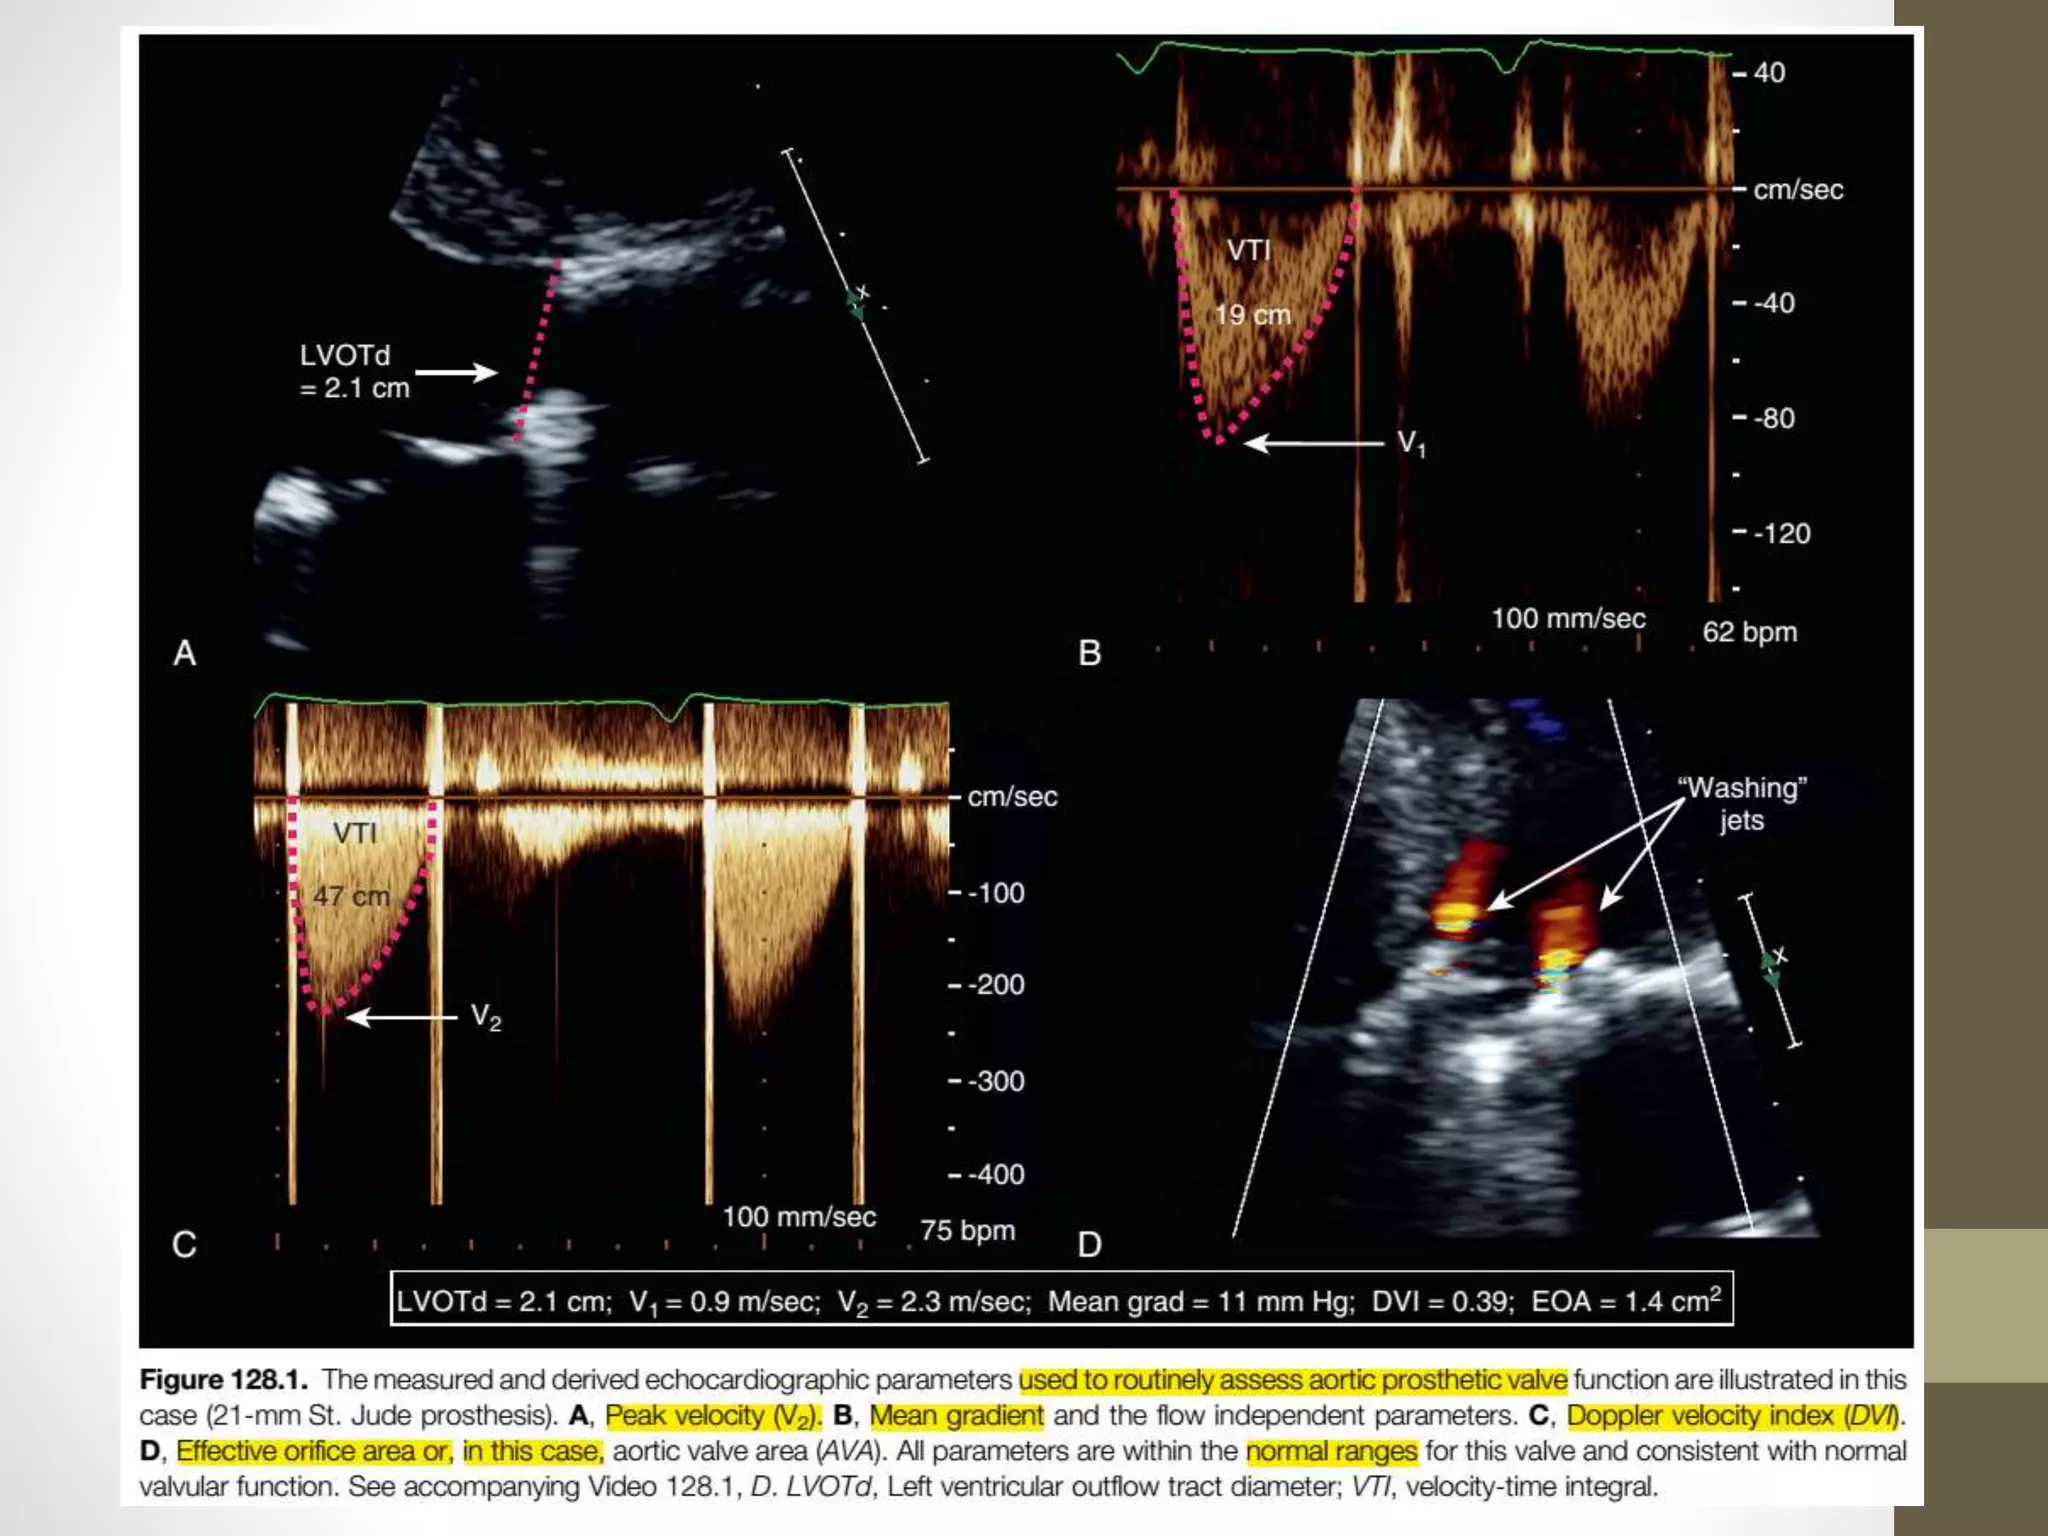

StandardTransthoracicEchocardiographicAssessmentOf

AorticProstheticValveFunction

• apical five chamber view can provide an improved view of the

leaflets/occluder, acoustic shadowing across the plane of the valve

is reduced

• As per ASE guidelines, the cross-sectional area is derived

from the LVOTd measured just underneath the prosthesis from

the parasternal long-axis view taking care to measure to the outer

margins of the valve sewing ring.

Doppler velocity index (DVI)

• a comparison of VTIPrV to VTI in the LV outflow tract

(VTILVOT)

• For prosthetic aortic valves, it is derived as VTILVOT/VTIPrV

• DVI as calculated for aortic valves is always less than unity

because velocity will always accelerate through the prosthesis;

it is normally greater than 0.25.